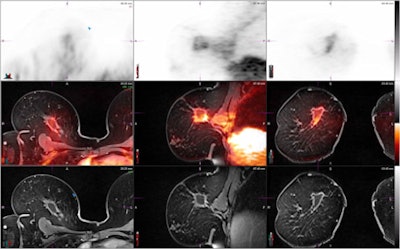

![]() |

| Localized breast image of a female patient in her 50s. FGD-PET image shows increased FDG uptake, which could represent residual malignancy versus postsurgical change. Fusion with the anatomically detailed T1-weighted postcontrast MR image shows increased uptake localized to a smoothly marginated seroma and is benign. |

NYU Langone scanned its first patient on the PET/MRI system in late July. The protocol called for the patient to undergo a PET/MRI exam after a PET/CT study to compare the performance of PET/MRI with PET/CT in detecting whole-body disease. In this case, the scans were performed for metastatic breast cancer.

The procedure is part of a larger study in which the facility is enrolling breast cancer patients who are undergoing FDG-PET/CT to assess systemic disease, either at the time of diagnosis or during or after therapy. The goal is to determine if PET/MRI can provide additional information to detect brain and liver metastases. One benefit is that PET/MRI exposes a patient to one-third the radiation dose of PET/CT. The principal investigator is Dr. Amy Melsaether, an assistant professor in the department of radiology.